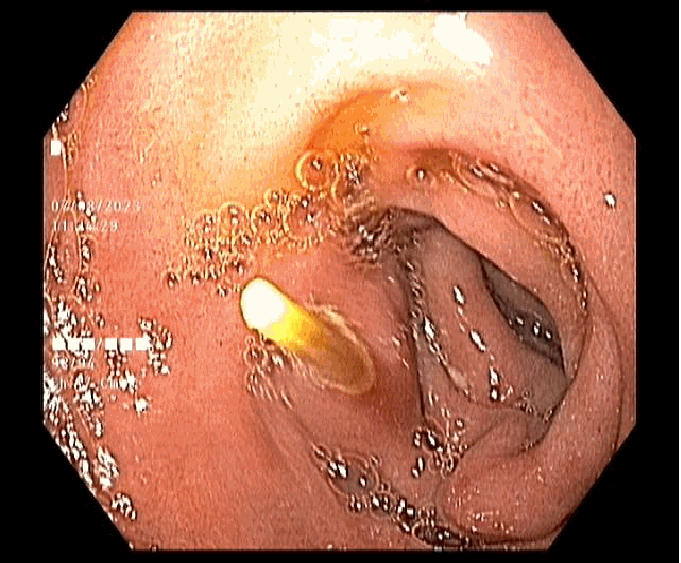

Nhận thấy tình trạng nguy cấp, ê-kíp nội soi ngay lập tức tiến hành nội soi an thần để gắp dị vật ra khỏi dạ dày của người bệnh. Sau khi thực hiện, các triệu chứng đau bụng đã thuyên giảm, ông Q. được tiếp tục theo dõi và xuất viện trong ngày.

Dị vật được gắp ra từ dạ dày người bệnh